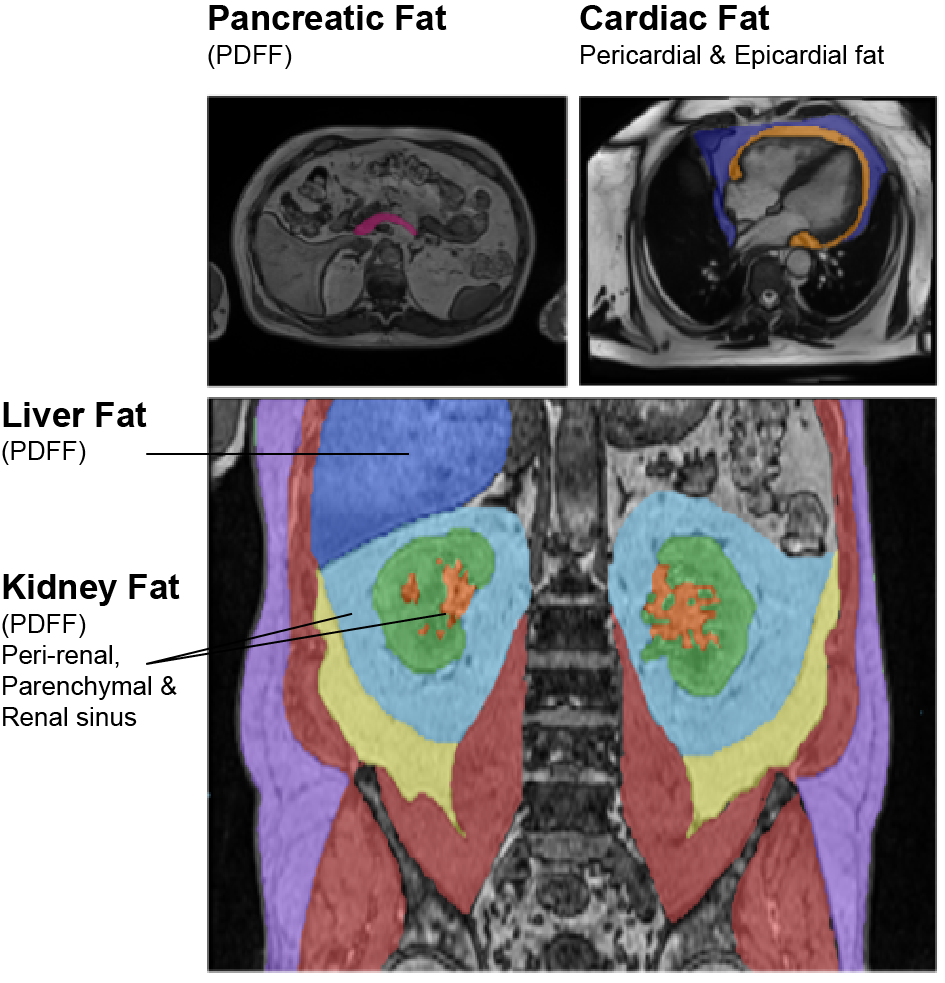

Ectopic fat – impairs organ health and is one of major factors in cardiometabolic disease development

Multi-organ ectopic fat

Pericardial fat

Epicardial fat

Liver fat PDFF

Pancreatic fat PDFF

Peri-renal fat

Renal sinus fat